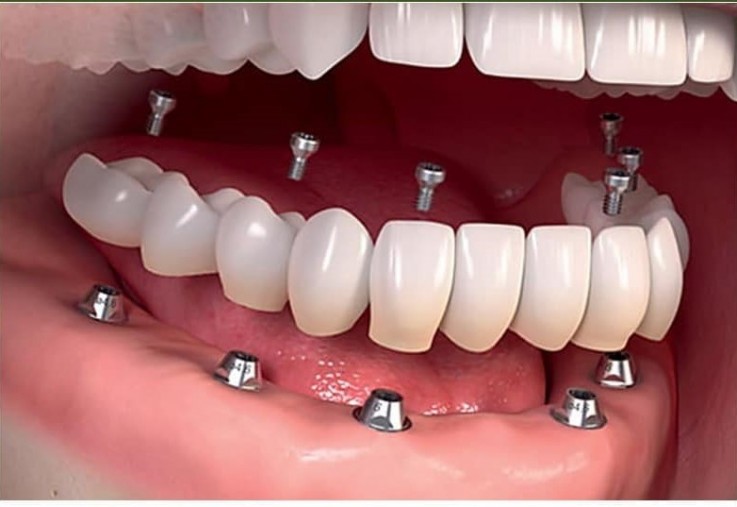

One of the best Dental Clinics in Visakhapatnam We are specialists in Full Mouth Rehabilitation using Crowns & Bridges,Implants, Dentures. We offer the best ethical & painless treatments across wide range of dental services like root canal treatment,wisdom teeth removal, cosmetic treatment, dental surgeries, tooth extractions, fillings, teeth whitening, bleaching,Periodontal surgeries (gum treatments), teeth cleaning, polishing, Child Dentistry. We use high quality dental materials and equipment but provide dental services at reasonable and affordable prices.'https://manohardentalcare.com Best Dental Clinics in vizag for root canal,cosmetic #treatment Procedures, wisdom #teeth Replacement removal, #dental surgeries, #tooth extractions, #fillings, whitening, bleaching, # Periodontal surgeries (gum treatments), #teeth cleaning,#polishing, #Child-Dentistry